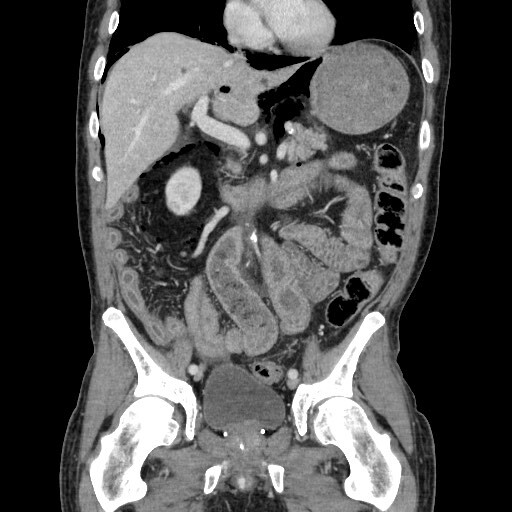

# Abdome: cólon e reto A colonografia por TC (CTC) vem sendo implementada para rastreamenteo do CCR. Vantagens? (5)

1. Minimamente invasiva; 2. Rápida; 3. Sem sedação; 4. Mínimo risco de complicações (perfurações / complicações cardiovasculares); 5. Sensibilidade aceitável em relação à colonoscopia para diagnóstico de pólipos clinicamente significantes e câncer colorretal (CCR)

# Abdome: cólon e reto **V ou F?** Para CCR e pólipos grandes (≥10 mm), a CTC oferece desempenho comparável à colonoscopia. Para pólipos intermediários (6–9 mm) e especialmente os menores, a colonoscopia continua superior.

Verdadeiro.